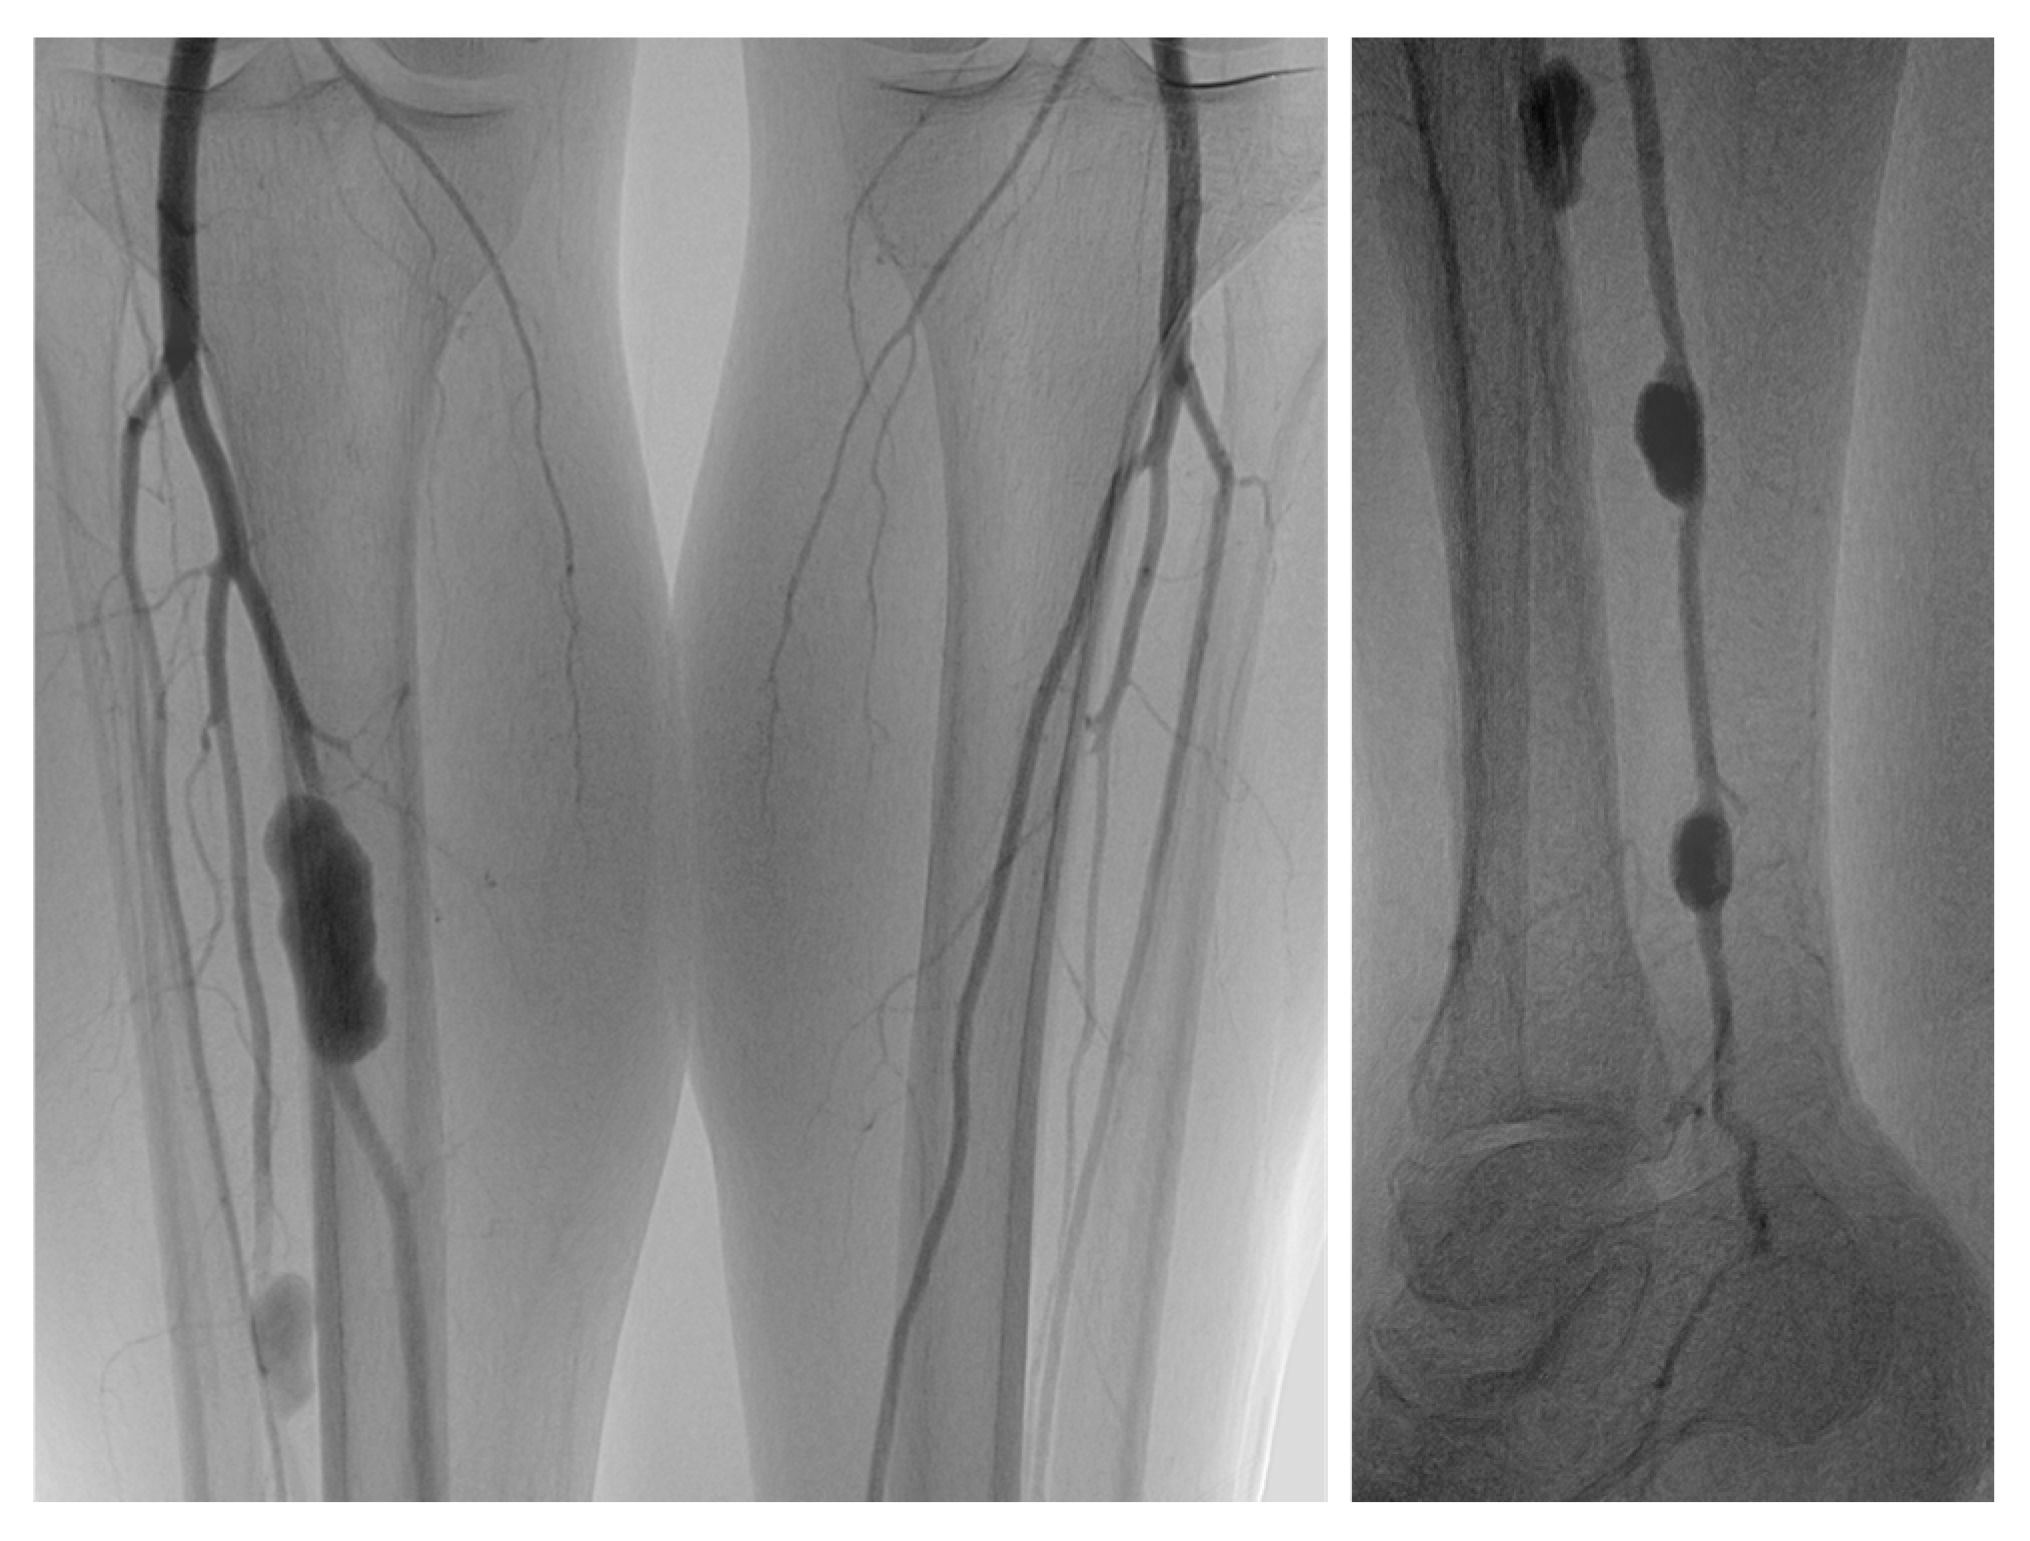

| Manuscript | Patient | Thromboembolectomy | Time * | PTPA Symptoms | PTPA Diagnosis | PTPA Treatment |

|---|---|---|---|---|---|---|

| Del Grande et al., 2001 [13] | Female; age: 89 years | Left above-the-knee femoropopliteal polytetrafluoroethylene bypass graft | 3 days | Painful, enlarging, pulsating hematoma above the ankle | DSA: peroneal artery; size: 2 × 4 cm | Retrograde embolization (direct puncture of the PTPA) with multiple microcoils (d = 2–3 mm) |

| Neary et al., 2002 [11] | Female; age: 78 years | Right deep and superficial femoral arteries | 7 days | Increasingly severe pain in the calf with reduced dorsiflexion | DUS + DSA: posterior tibial artery; size: no data | Thrombin injection (500 IU) |

| Corso et al., 2003 [9] | Male; age: 65 years | Right branch of axillobifemoral bypass graft and right superficial femoral artery | 1 day | Vivid pain and palpable pulsatile mass in the calf, paresthesia of the foot | DUS + DSA: posterior tibial artery; greatest d = 11.5 cm | Thrombin injection (6000 IU) |

| Sugimoto et al., 2004 [17] | Male; age: 63 years | Right femoropopliteal polytetrafluoroethylene bypass graft | 3 days | Hematoma, pain, and pulsating mass in the posterior lower calf | DSA: peroneal artery; size: no data | Occlusion of the feeding artery with microcoils (n = 2, d = 5 mm) proximal to the PTPA |

| Sadat et al., 2007 [10] | Male; age: 68 years | Right superficial femoral artery | 2 weeks | Pain in the lower part of the leg and expansile swelling on the anteromedial surface of the leg, 5 cm above the ankle | DUS + DSA: peroneal artery; size: 5.1 × 2.4 cm | Occlusion of the feeding artery with microcoils (n = 5, d = 4 mm) proximal and distal to the PTPA |

| Nenezić et al., 2009 [15] | Female; age: 82 years | Right superficial femoral artery | 1 month | Painful pulsating mass in the anterior portion of the calf | CTA: anterior tibial artery; size: no data | Great saphenous vein interposition grafting |

| De Santis et al., 2013 [12] | Male; age: 68 years | Right popliteal artery | 2 months | Tender, painful, pulsatile mass in the mid-anterior aspect of the leg | DUS + CTA: anterior tibial artery; size: 3.8 × 6.6 cm | Covered balloon-expandable stent (4 × 19 mm) implantation |

| Kaczynski et al., 2016 [14] | Male; age: 78 years | Right popliteal artery and tibioperoneal trunk | 10 weeks | None | DUS + CTA: peroneal artery; size: 1.3 × 3.6 cm | Occlusion of the feeding artery with microcoils (d = 3–5 mm) proximal and distal to the PTPA |